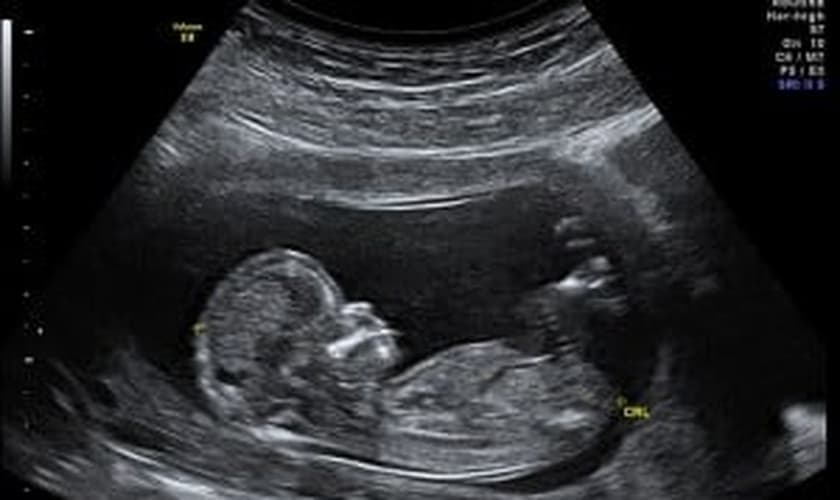

Segundo relata o site "Christian News Network", Michelle Macaulay passou pela gestação de sua segunda filha com seu marido, ao final de 2012. Ao longo de 12 semanas de exames, os médicos descobriram que o bebê tinha uma doença genética e disseram que o que a criança era "incompatível com a vida."

"Eles disseram que o bebê tinha um higroma cístico e, por isso, o sistema linfático não se desenvolveria adequadamente", disse ela ao Daily Record.

"Quando me disseram que o bebê era 'incompatível com a vida', isto foi simplesmente horrível, porque, olhando para aquela tela, eu via que uma vida já havia começado", disse ela. "É apenas uma enorme termo para chamar ninguém, muito menos um bebê crescendo dentro de você."